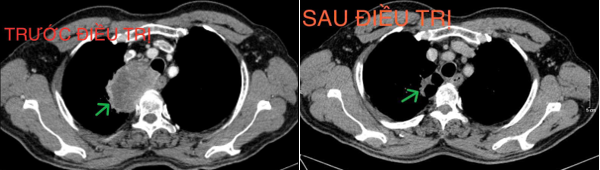

- Chụp cắt lớp vi tính lồng ngực (20/08/2024): Thùy trên phổi phải có khối đặc kích thước ~ 67x39mm, bờ không đều, ngấm thuốc sau tiêm không đồng nhất, dày tổ chức kẽ dạng lưới và kính mờ xung quanh, lân cận có nốt kính mờ đường kính ~5mm, phát triển vào trung thất, đẩy khí quản và thực quản lệch trái, có phần không rõ ranh giới với thành thực quản đoạn ngang mức. Phổi trái giãn phế nang trung tâm tiểu thùy và cạnh vách chủ yếu thùy trên. Trung thất, rốn phổi phải có vài hạch kích thước ~13x17mm, ngấm thuốc không đều sau tiêm.

Hình 1. Hình ảnh khối u thùy trên phổi phải (mũi tên xanh) kích thước 67x39mm, bờ không đều, ngấm thuốc sau tiêm không đồng nhất.

+ Chụp cắt lớp vi tính lồng ngực (16/12/2024): Hình ảnh cấu trúc dạng hang thùy trên phổi phải, kích thước ~36x22x44mm, bờ không đều, thành dày không đều, ngấm thuốc không đồng nhất sau tiêm. Hạch trung thất và rốn phổi phải.

Hình 6. Khối u trước và sau điều trị (mũi tên xanh), sau điều trị kích thước khối u giảm còn khoảng 36x22x44mm

Hình 7. Hạch trung thất trước và sau điều trị (mũi tên xanh), kích thước hạch sau điều trị giảm xuống còn dưới 10mm đường kính trục ngắn.

*Kết luận: Ca lâm sàng trên cho thấy một trường hợp bệnh nhân nam lớn tuổi, chỉ số toàn trạng (Performance Status - PS) 1, vào viện với tình trạng khó thở và đau ngực nhiều, được chẩn đoán Ung thư phổi không tế bào nhỏ giai đoạn IIIB. Sau 4 chu kỳ hóa trị liệu với phác đồ Docetaxel - Carboplatin, bệnh nhân đạt được đáp ứng bệnh một phần, khối u giảm khoảng 50% kích thước so với trước khi điều trị, kích thước hạch trung thất giảm và nhiều hạch không còn nhìn thấy trên phim chụp cắt lớp vi tính. Sau điều trị bệnh nhân hết các triệu chứng lâm sàng, thể trạng được cải thiện và sinh hoạt trở lại bình thường. Bệnh nhân tiếp tục được đánh giá lên kế hoạch điều trị tiếp theo.